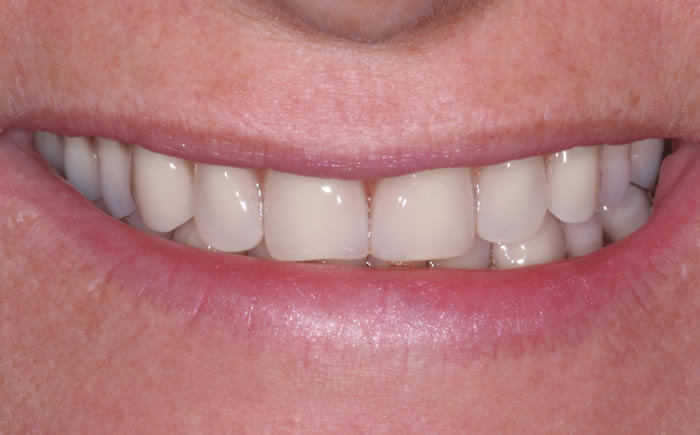

Before & After Gallery

The images below show examples of the different types of work carried out at the Street Lane Dental & Implant Clinic. All the images are of real patients of the Clinic treated by Dr Roberts and our Hygienist's.

Front teeth replaced by dental implants

Dental implants used to replace two upper front teeth